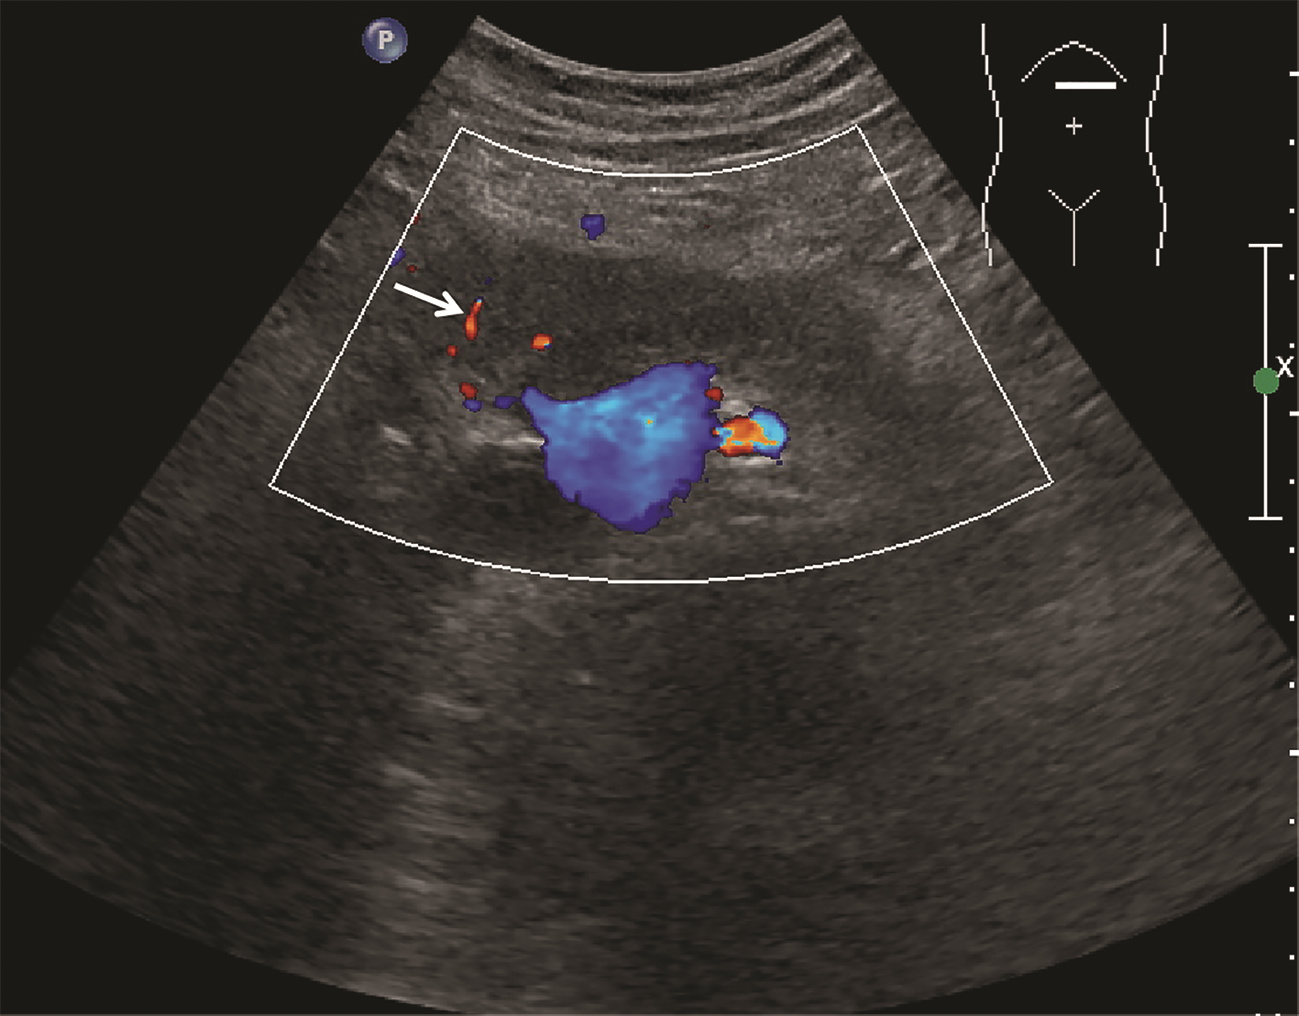

Ultrasound findings and contrast-enhanced ultrasound findings of mass-type autoimmune pancreatitis versus pancreatic ductal adenocarcinoma

Xiangliu OUYANG, Yunxia HAN, Lichun ZHENG, Yingchun ZHAO, Xinyu SHEN, Wenjun ZHANG, Yanbin WANG

2022, 38(6): 1351-1355. DOI: 10.3969/j.issn.1001-5256.2022.06.025

Abstract(1427) HTML (553) PDF (3738KB)(50)

Abstract:

Objective  To investigate the value of ultrasound and contrast-enhanced ultrasound (CEUS) in the differential diagnosis of mass-type autoimmune pancreatitis (AIP) and pancreatic ductal adenocarcinoma (PDAC).  Methods  A retrospective analysis was performed for the clinical data, ultrasound findings, and CEUS findings of 11 patients with mass-type AIP who were diagnosed in Tangshan Workers' Hospital from January 2015 to December 2020, and their characteristic manifestations were analyzed and compared with the data of 23 patients with PDCA. The chi-square test was used for comparison of categorical data between two groups.  Results  For the 11 patients with mass-type AIP, CEUS had a diagnostic accuracy of 63.64%, and all of these patients had hypoechoic single lesions; the patients with clear boundaries, regular morphology, pancreatic duct dilatation or cutoff, and blood flow signal accounted for 54.55%, 63.64%, 18.18%, and 36.36%, respectively, while in the PDCA group, such patients accounted for 30.43%, 34.78%, 78.26%, and 21.74%, respectively, and there was a significant difference in the presence or absence of pancreatic duct dilatation or cutoff between the two groups(χ2=11.089, P < 0.05), with no significant differences in the other indices (all P > 0.05). For the 11 patients with mass-type AIP, CEUS showed that 7 patients (63.64%) had hyperenhancement and 4 (36.36%) had iso-enhancement in the arterial phase, and 5 patients (45.45%) had hyperenhancement in the arterial phase and 6 (54.55%) had iso-enhancement in the venous phase; for the 23 patients with PDCA, 22 (95.65%) had hypoenhancement of lesions in both arterial and venous phases, and there were significant differences in the enhancement pattern in arterial and venous phases between the two groups (χ2=30.345 and 30.084, both P < 0.05).  Conclusion  The enhancement pattern of CEUS and the presence or absence of pancreatic duct dilatation or cutoff have a relatively high value in the differential diagnosis of mass-type AIP and PDCA.